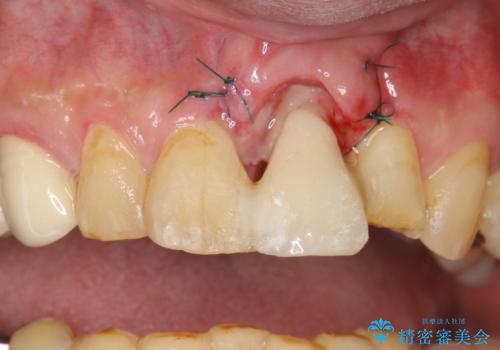

左上1が水平的に割れている状態で、歯冠を取り除くと神経が露出しており、唇側はかなり歯肉縁下で破折しており、そのままではかぶせものを入れるのは難しい状態でした。

根管治療をした上で歯を引っ張りだして(エクストリュージョン)、その後、骨外科にて歯周組織を整えた上で、かぶせものを入れていく治療計画をたてました。